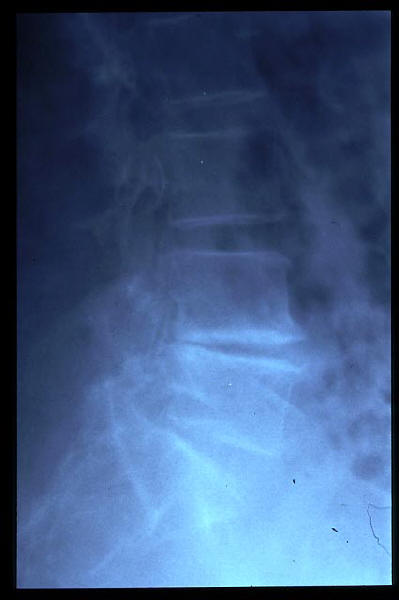

Osteoporosis. Cifosis.

Escoliosis, artrosis, aplastamiento...

Fractura vertebral, aplastamiento

Acuñamiento vertebral traumático

Aplastamiento vertebral. Gas. Osteoporosis.

Aplastamiento vertebral. Osteoporosis.